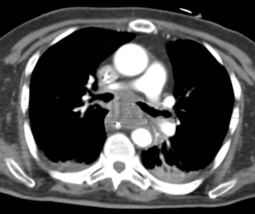

Neoplasia de carina principal